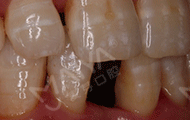

手术当天,我先和在场的朋友们分享了我的缺牙感受,然后进了手术室,除了麻醉的时候有点感觉外,种牙没有一点痛感,自己小咪了几分钟牙就种好了,而且出血量微乎其微,专家们技术真的非常高超。看着镜子里面的牙齿,发现跟周围的真牙完美的融合了,一点也看不出假牙的样子,特别美观舒服。回到现场,大家问我种牙什么感觉,我最想说的就是:种牙真的不疼,而且整个手术时间很快,要相信我们的医生和技术。

经过数字化的拍片检查后发现,我的牙周情况还是蛮不错的,可以用MAC数字化精确种植牙实现8分钟种稳一颗牙,而且工作人员说我可以作为直播案例主角分享自己的故事,感到非常荣幸。